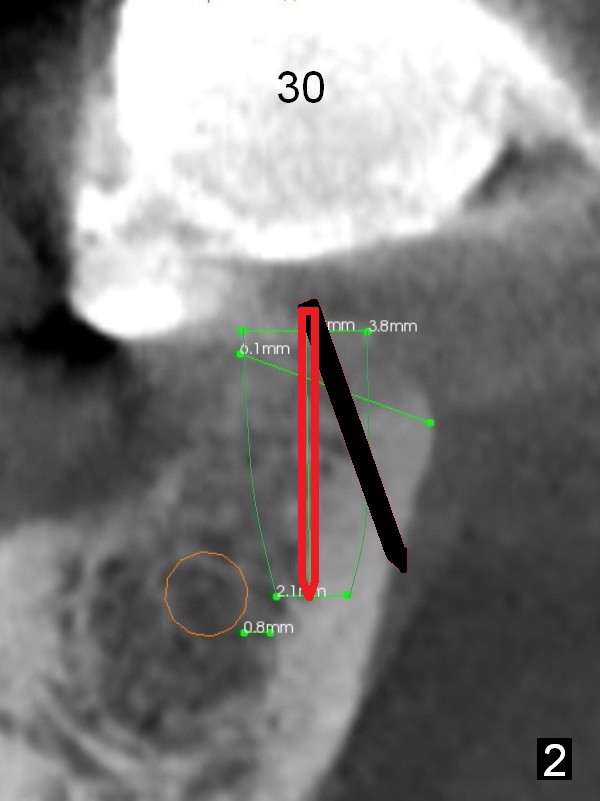

At the site of #30, the lingual plate perforates in the early stage of osteotomy (Fig.1 red arrow).  As indicated by the thick lingual plate, the osteotomy turns out to be difficult.  The trajectory is corrected immediately (Fig.2 red) and with control so that the Inferior Alveolar Canal (brown circle) will be not be violated.  The perforation is repaired with Osteogen plug (Fig.3 white) and nearby autogenous bone (red circles) before placement of a 3.8x8 mm implant (green).